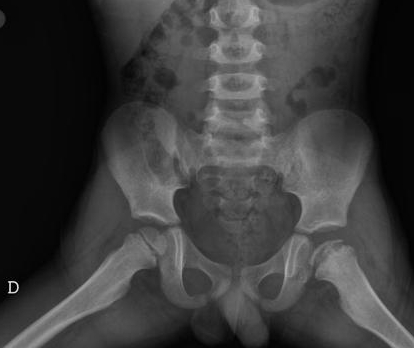

SCFE

13 yo

growth spurt, fat. Nontraumatic joint pain.

Frog-leg xray

Surgery

SCFE: slipped capital femoral epiphysis

frog leg xray: